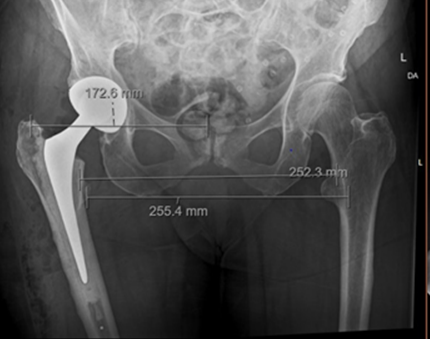

Complex Reconstruction of Post-traumatic Fracture Dislocation Hip: The Anchor Total Hip Arthroplasty Following Failed Index Surgery

Vijay G Goni , Deepak Kumar , P K Vivek , Manjunath Nishani , M Harshith , V S Sumukha ………………………………p.182-187